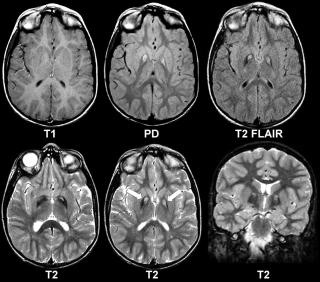

Липома головного и спинного мозга

Липомы головного мозга также выявляют случайно, когда у пациентов старшей возрастной группы проводят МРТ или КТ мозга по каким-то другим причинам, например, при нарушении когнитивных функций, эпилепсии. Липомы могут быть обнаружены в любом отделе мозга, тем не менее 50% – это перикалозальные липомы, в свою очередь 45% которых ассоциированы с агенезией мозолистого тела. 25% составляют липомы квадригименальной цистерны и 15% – липомы супраселлярной цистерны. Так как липомы мозга не имеют симптомов, хоть и часто сочетаются с какими-то пороками, например, агенезией мозолистого тела, то и лечения они не требуют. Хирургическое лечение сопряжено с большим риском осложнений и не имеет никаких преимуществ. Если возникают гидроцефалия или судорожный синдром, то лечение проводят по общим правилам.

Липома мозолистого тела головного мозга. Фото: Journal of neurosciences in rural practice / Open-i (Attribution-NonCommercial-ShareAlike 3.0 Unported)